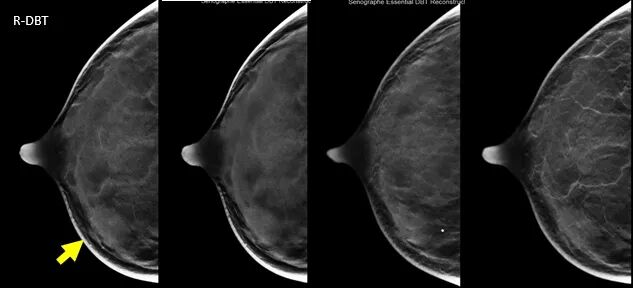

1.肿块的显示

病例1:CC,MLO/DBT显示:肿块、形态、边缘、密度、大小、内部结构显示显著优于MG。病理:乳腺粘液癌。